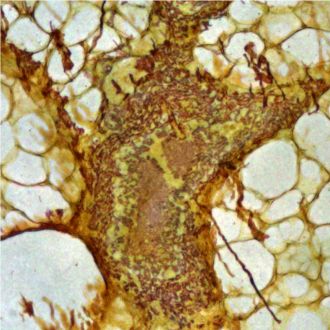

Unstained cancerous tissue viewed using a NanoMslide

“Recent breakthroughs in nanotechnology have allowed us to manipulate the interaction of light with biological tissue so that abnormal cells appear to have a different colour to healthy ones. Comparing images from our slides to conventional staining is like watching colour television when all you’ve seen before is black and white.”

“For the first time I saw cancer cells just popping up at me. They were a different colour from the surrounding tissue, and it was very easy to distinguish them from surrounding cells.”